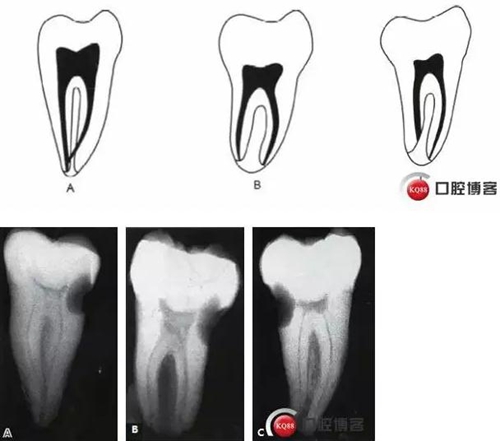

這種分類方法將下頜第二磨牙分為3 型:

I型:融合型,X線片上見2個(gè)根管,但在根尖區(qū)融合。

II型:分離型,X線片見2個(gè)根管且互相獨(dú)立。

III型:不對稱型,X線片上雖有2個(gè)根管互相獨(dú)立,但一長一短,互不對稱。

6.jpg